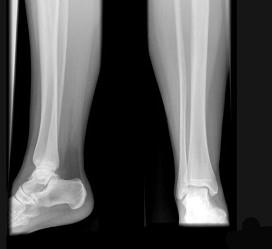

女,请根据其正常小腿影像图像,判断其最可能的年龄 ( )A、12岁左右B、8岁左右C、20岁左右D、16岁左右E、4岁左右

问题 女,请根据其正常小腿影像图像,判断其最可能的年龄 ( )

选项 A、12岁左右 B、8岁左右 C、20岁左右 D、16岁左右 E、4岁左右

答案 C